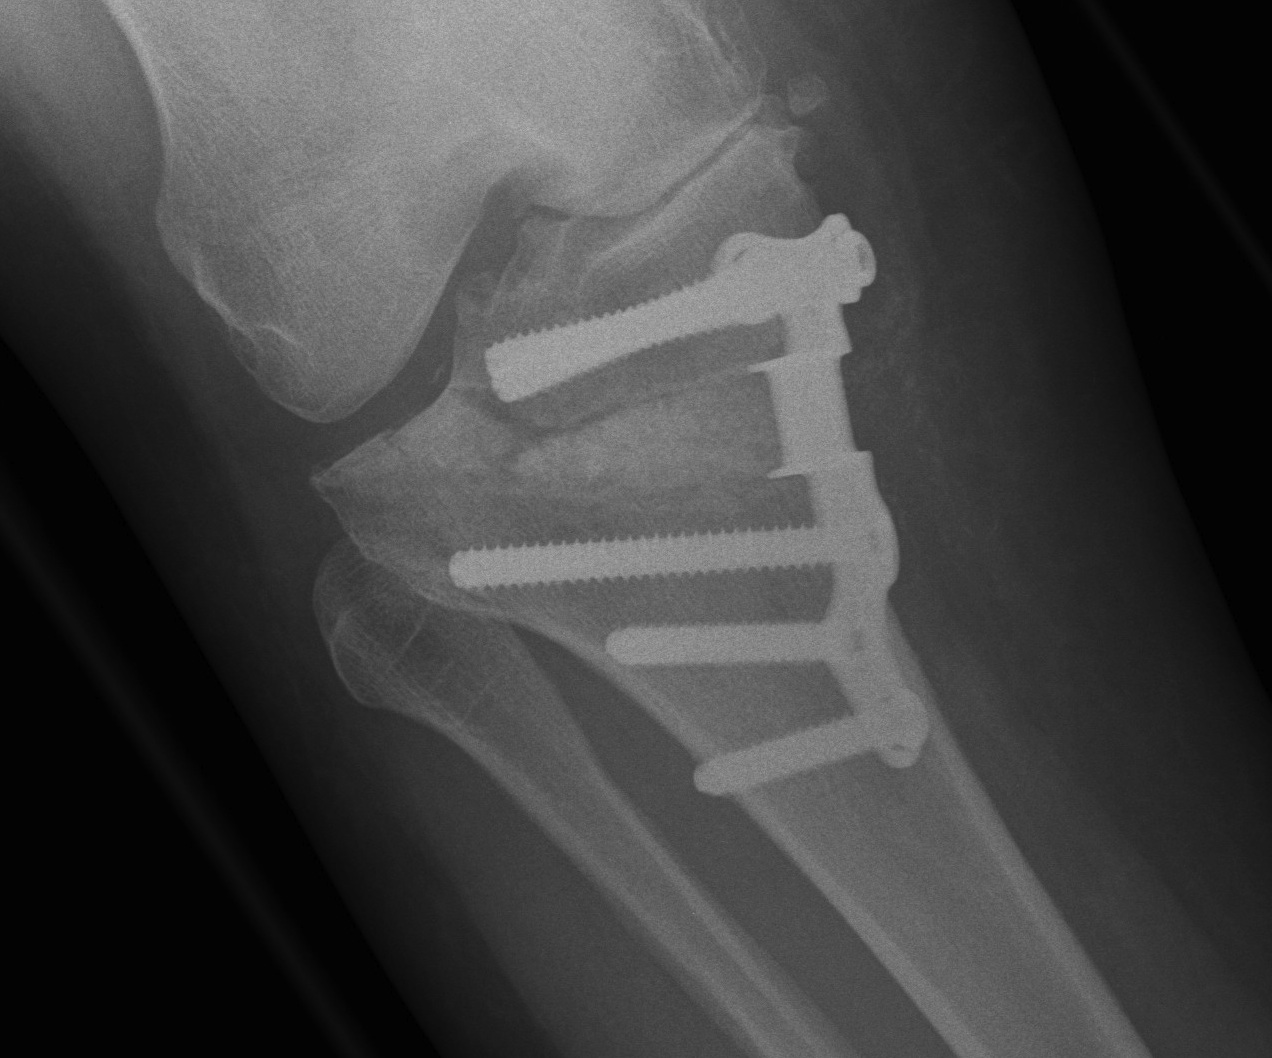

Stabilisation

- locking plates

- +/- autograft / allograft / synthetic bone graft

Arthrex Locking Puddhu plate PDF

Arthrex ContourLock system PDF

Management

Type I: limit weight bearing 6 weeks

Type II / displacement: lateral plate

Instability

- place a Richards staple / plate over lateral fracture site